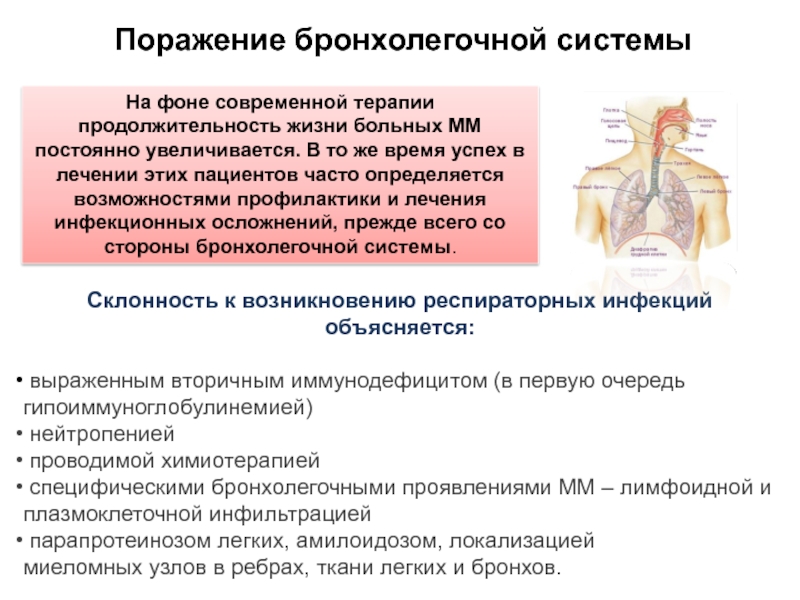

Фотографии заболеваний бронхолегочной системы

Раздел: Необычные решения